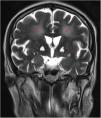

Medicina Clínica (English Edition) Billateral globus pallidus ischemia: A case report

Billateral globus pallidus ischemia: A case report

Isquemia bilateral de globos pálidos: estudio de un caso